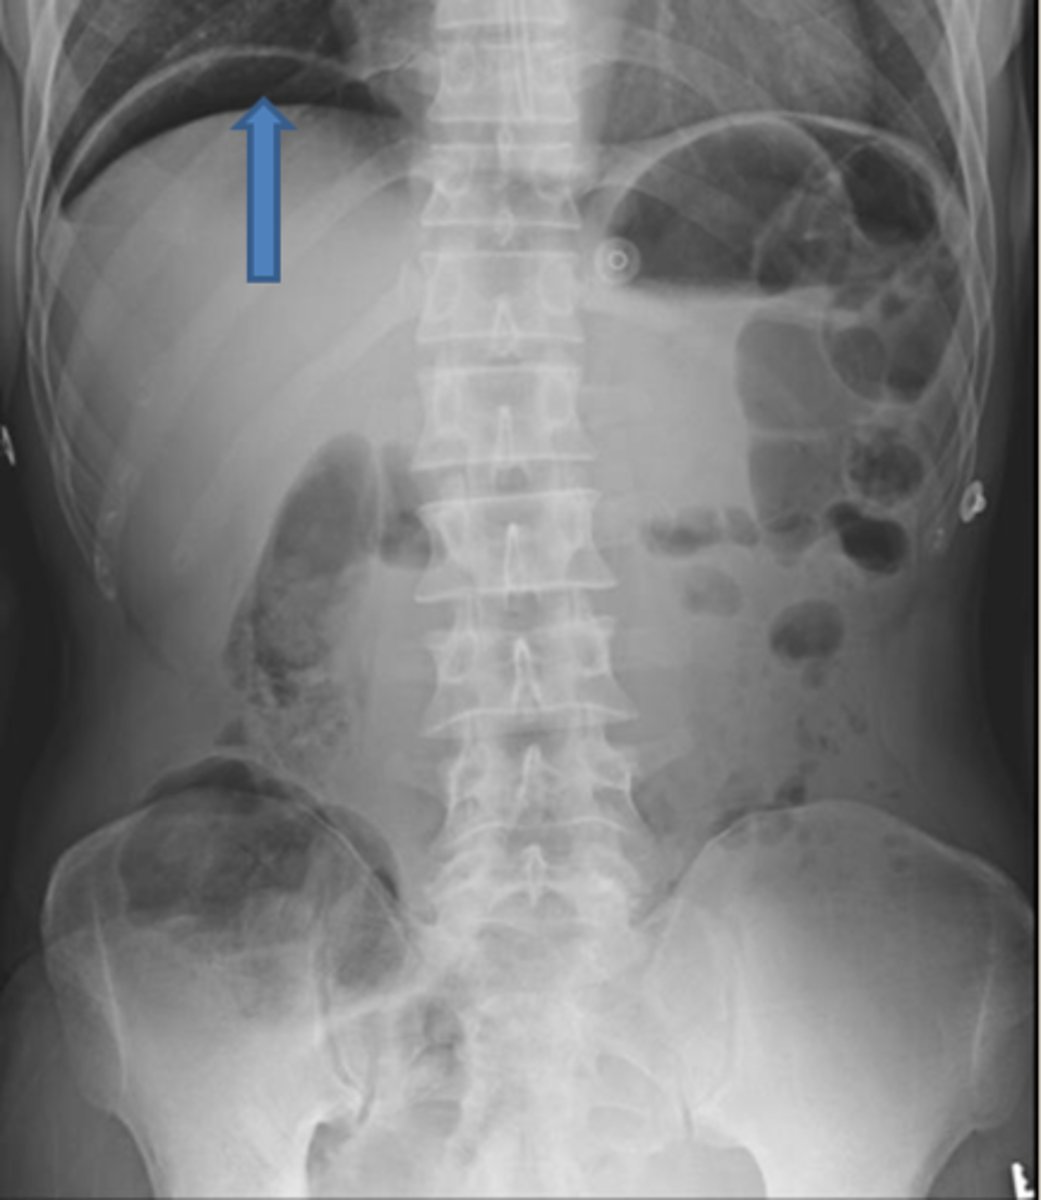

HEPATOMEGALY

BLACK ARROWS: displacement of all bowel loops from RUQ to iliac crest and across the midline.

Hepatomegaly is usually indicated by displacement of all bowel loops from RUQ to the iliac crest and across the midline, as in this pt with cirrhosis.

Sometimes the liver can be so enlarged that it will be obvious even on conventional radiographs